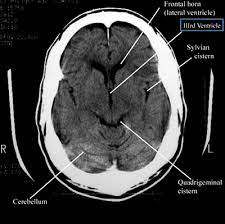

A Head CT Scan, or Computed Tomography Scan of the head, is a non-invasive and highly detailed diagnostic tool. It uses sophisticated X-ray technology to capture cross-sectional images of the brain and skull, assisting in diagnosing various conditions such as tumors, brain injuries, and other neurological disorders. For someone like Anita, the scan was a beacon of hope, offering the possibility of understanding her condition with precision.

After a thorough consultation, Anita's doctor recommended a Head CT Scan. The decision was not made lightly; it was a step towards clarity and resolution. The process was straightforward and quick. Anita lay on a table that slid smoothly into the doughnut-shaped machine. The entire procedure was over within minutes, painless and efficient.